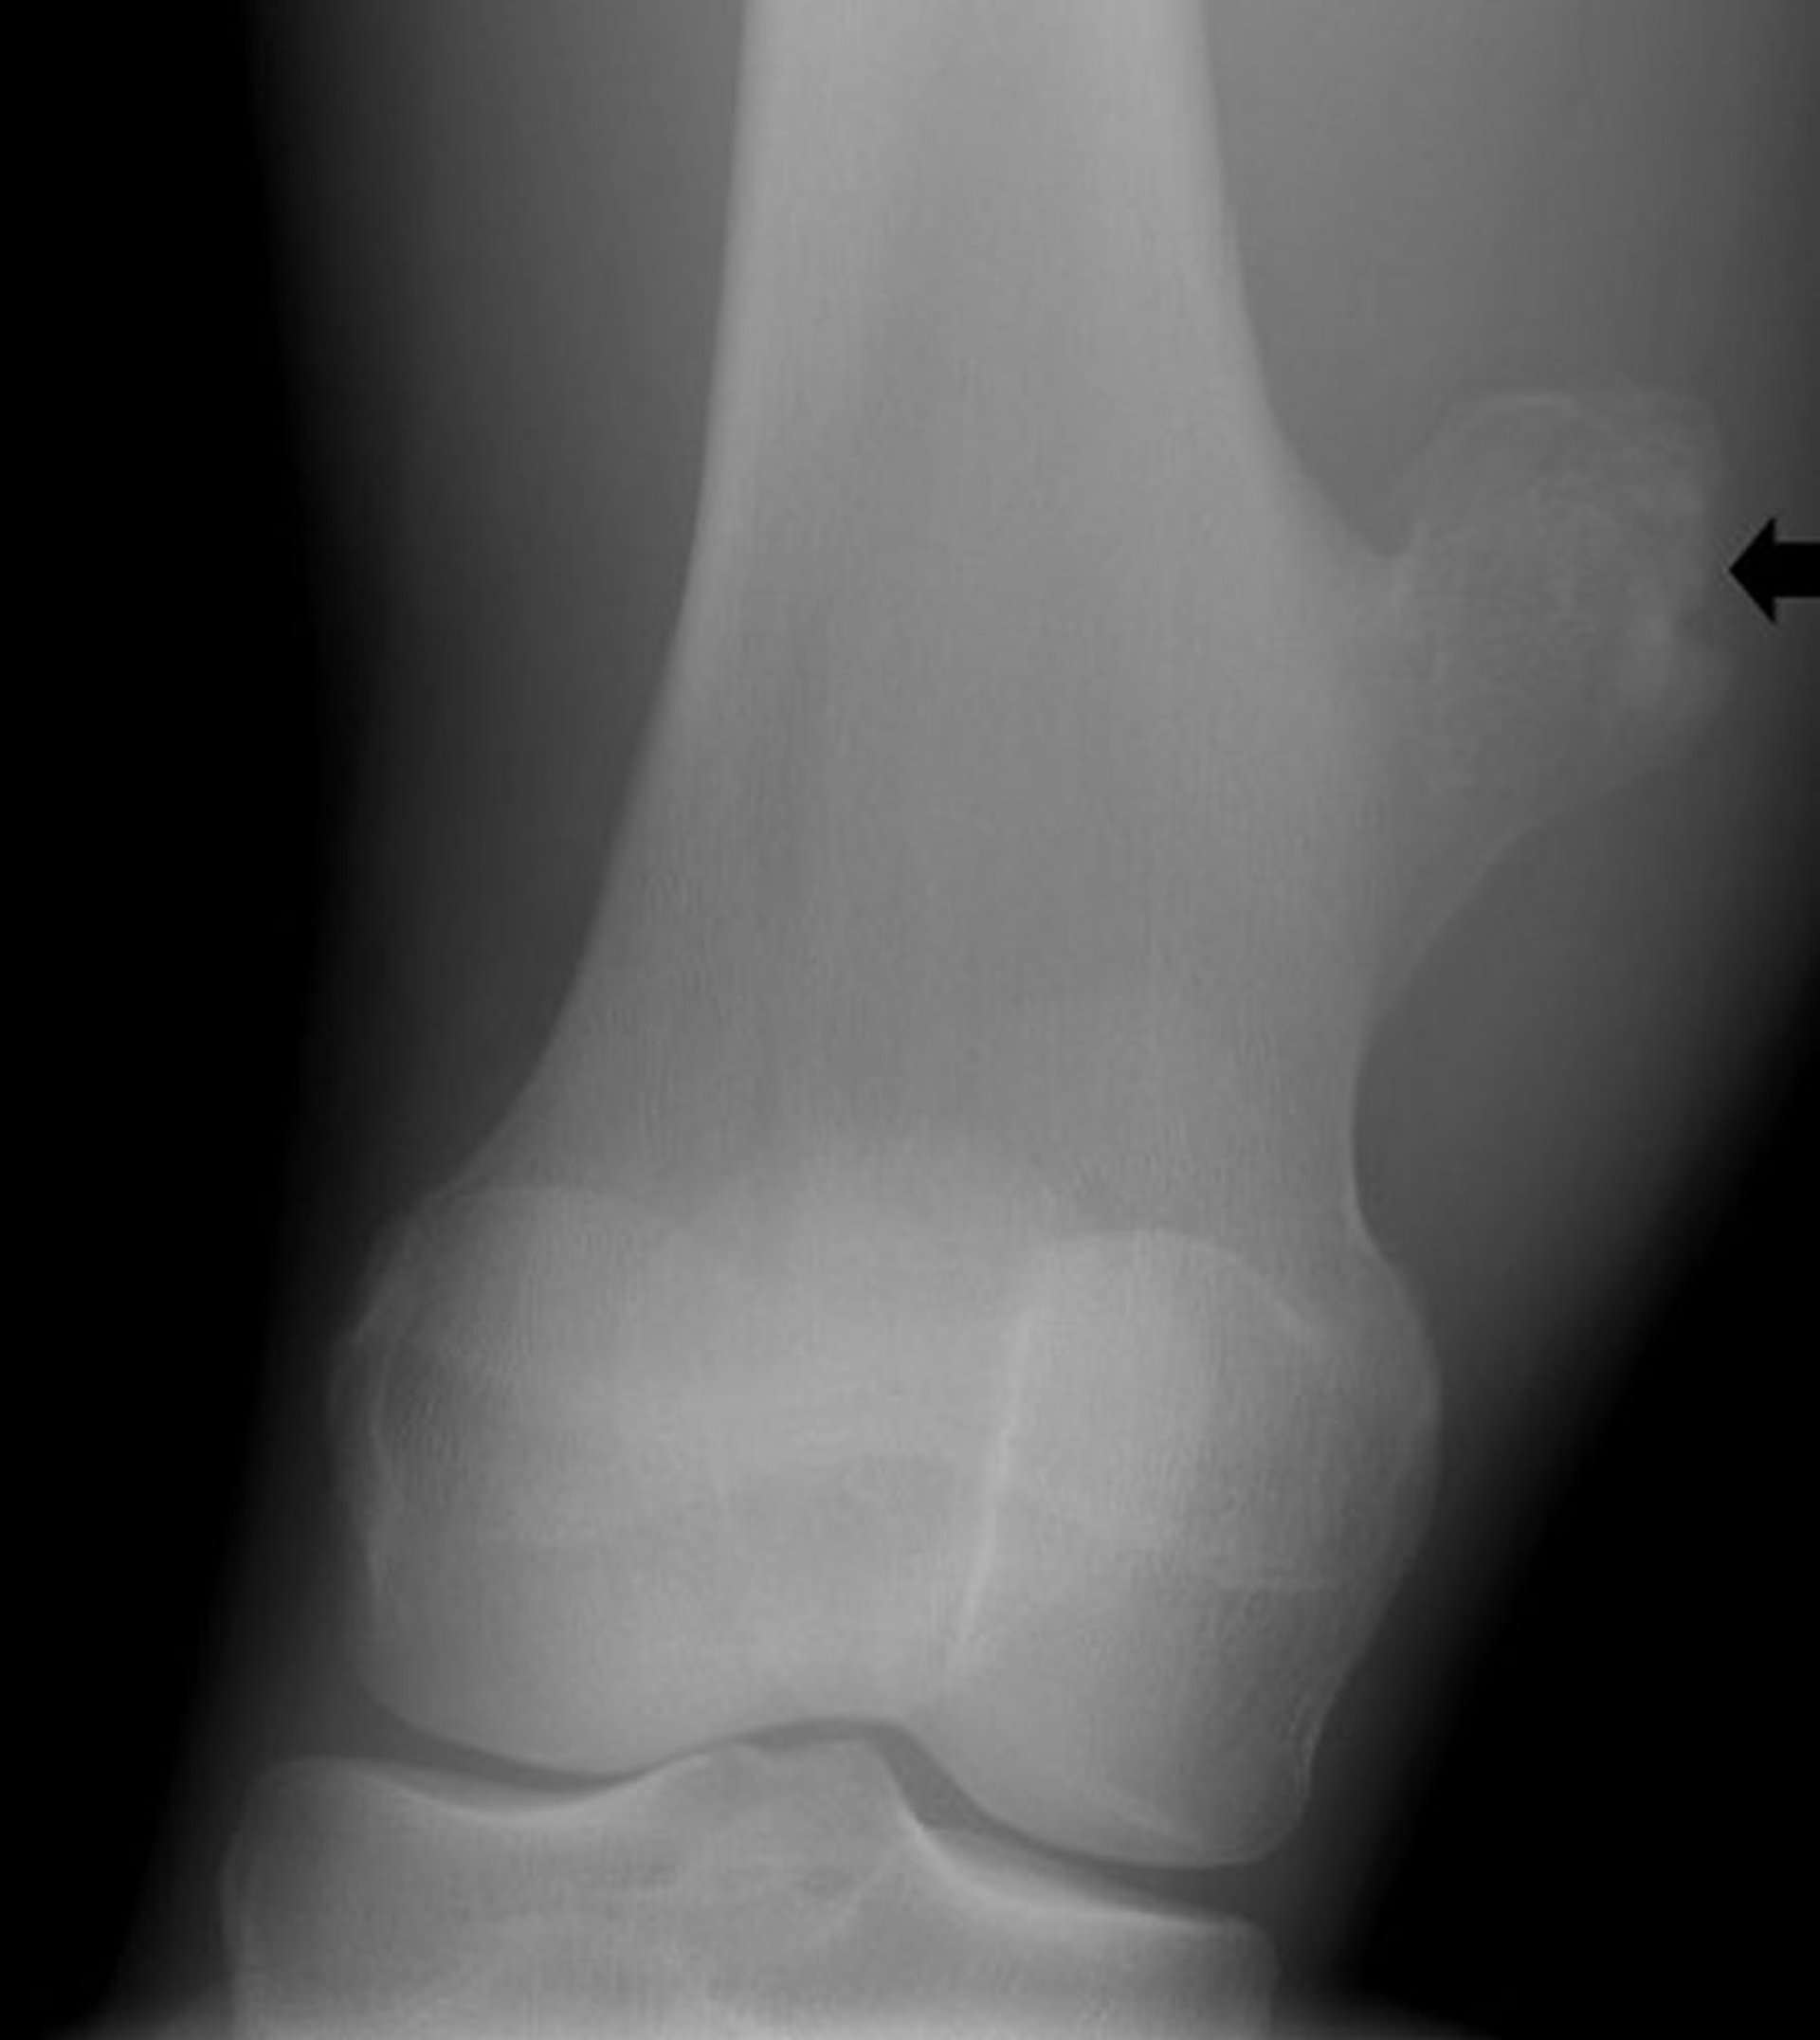

Osteochondroma of the Knee

Phim chụp X-quang đầu gối này cho thấy một khối xương phát triển (mũi tên) từ xương đùi phía trên khớp gối, phù hợp với u xương sụn.

Hình ảnh do bác sĩ Michael J. Joyce, và bác sĩ Hakan Ilaslan cung cấp.